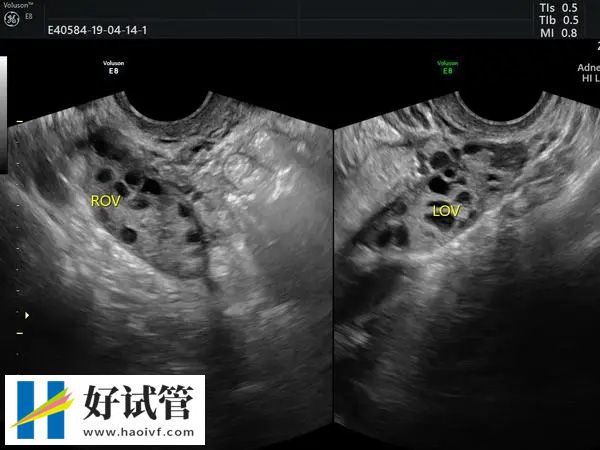

促排药能够刺激女性卵巢排放更多的卵泡,增加成功率。这些药物通常由注射或口服给予。在这个过程中需要密切监视女性身体情况,包括血液激素水平和超声检查。

在促排5天后需要再次返院检查看卵泡的大小,如果卵泡的大小已经达到18-20mm的话,那么就需要打夜针,一般就是使用艾泽或者是达必佳促进卵泡的最终成熟。